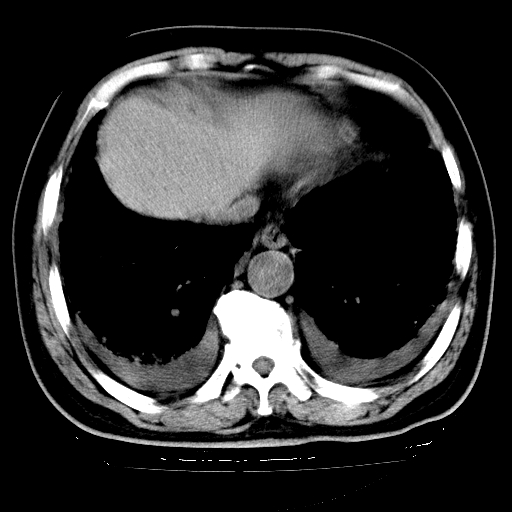

男,68岁,咳嗽、胸闷、发烧三天,查体:双肺散在湿罗音。

首先考虑特发型肺间质纤维化;两侧少量胸腔积液。

依据:1、两肺广泛条索状、网格状、蜂窝状改变。

1.双肺间质纤维化并感染;

2.双肺慢支炎肺气肿;

3.支扩并感染;

4.肺原性心脏病;

5.双侧胸腔少量积液;双侧胸膜增厚。

双肺多发条索状、网格状及小灶状密度增高影。考虑慢支合并感染.间质纤维化,双侧少量胸腔积液

两肺广泛条索状、网格状、蜂窝状改变。肺间质纤维化,肺心病,双侧胸腔积液